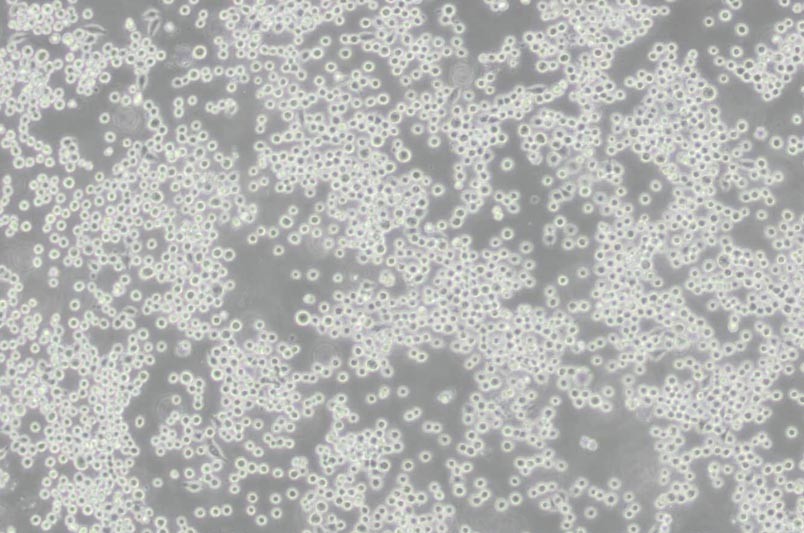

COLO-205人結(jié)腸癌細(xì)胞

細(xì)胞形態(tài) :上皮細(xì)胞樣

生長(zhǎng)特性 :半貼半懸